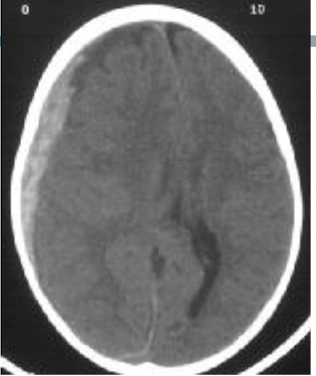

9

Q

where is the blood

A

intracerebral

How well did you know this?